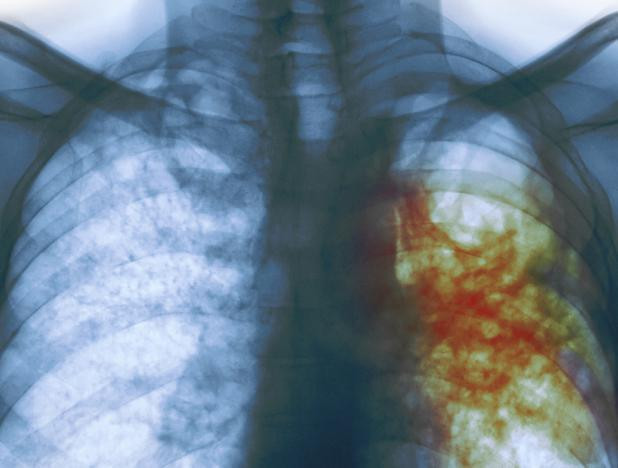

6 ay boyunca öksürük ateş dinmedi akciğerinden prezervatif çıktı! - Resim: 1

27 yaşındaki bir kadın altı ay boyunca aralıksız devam eden öksürük, ateş ve balgam şikayeti üzerine antibiyotik aldı. Doktorlar onu grip, soğuk algınlığı tedavisine yönlendirdiler. Daha sonra tam teşekkülü bir test yapıldı.

Genç kadına daha sonra tüberküloz teşhisi konuldu. Ve tüberküloz tedavisi oldu. Ancak genç kadının öksürükleri, ağrıları ve diğer belirtiler bir türlü geçmek bilmedi. Ta ki son yapılan teste kadar.

Aylardır grip belirtileri gösteren genç kadın gerçeği öğrenince şoke oldu. Bütün bunlara akciğerine kaçmış bir prezervatifin sebep olduğu öğrenildi.